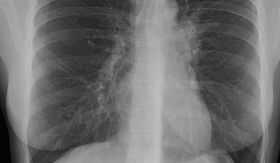

Romania s-a mentinut pe primul loc la numarul cazurilor de TBC inregistrate la suta de mii de locuitori, in ultimii 20 de ani, in continentul european. In conditiile in care tarile Uniunii Europene au 80.000 de cazuri de TBC, Romania contribuie la aceasta cifra cu 25.000 de cazuri. Conducerea Programului National de Control al Tuberculozei nu crede ca situatia se va schimba vreodata, anunta, joi, Realitatea TV.

In 2007, incidenta cazurilor de TBC a fost de 106,4 la suta de mii de locuitori, iar in 2008 de 105,9 la suta de mii de locuitori. In primele noua luni ale anului trecut incidenta cazurilor de TBC a scazut usor pana la 106,3 cazuri la suta de mii de locuitori, fata de aceeasi perioada a anului 2008, cand s-au inregistrat 109,9 cazuri la suta de mii de locuitori.